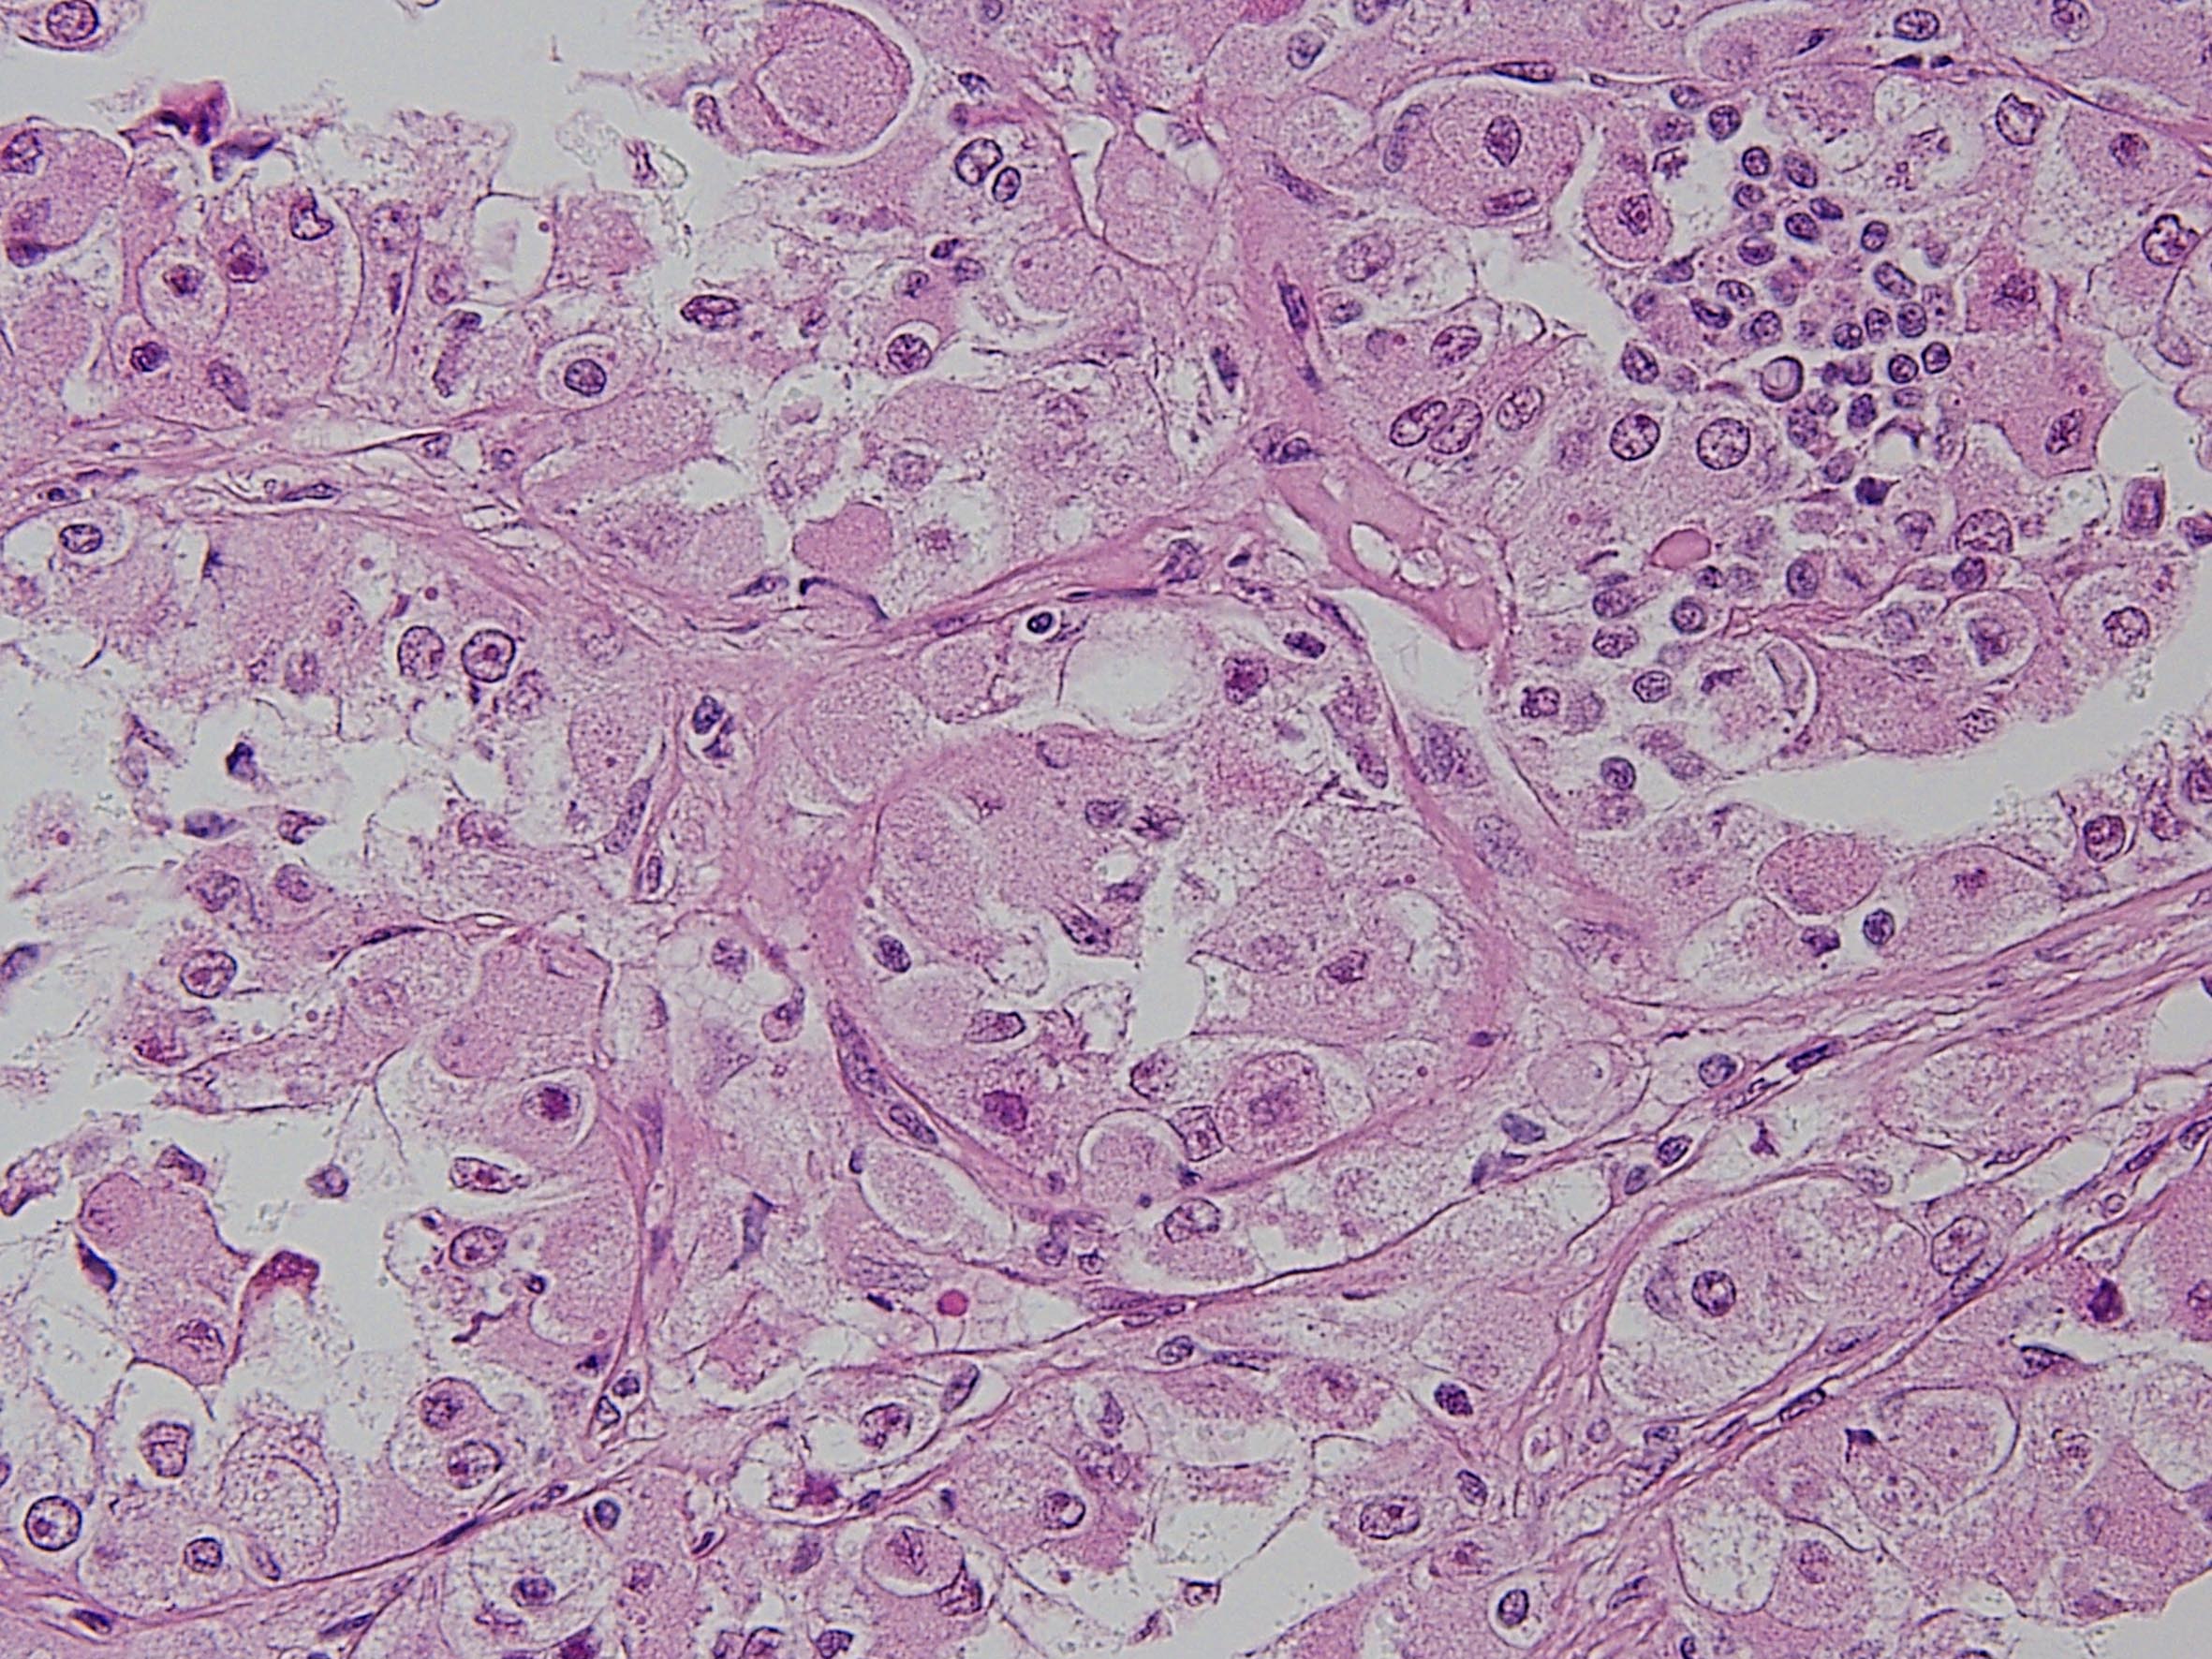

Consensus grade: MiT Family translocation carcinoma

MiT family translocation renal cell carcinoma. t(6;11) translocation

Section courtesy of Dr P Argani